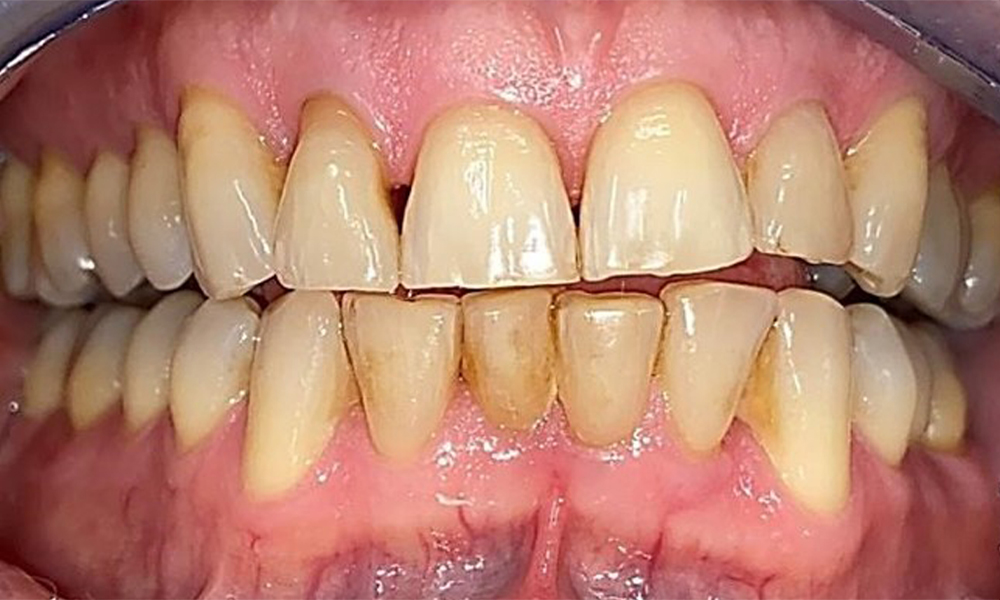

Фронтален изглед със загуба на интерденталната папила между 12 и 11.

Фиг. 2 Фронтален изглед със загуба на интерденталната папила между 12 и 11 © д-р Р. Крапф

Пациентът има пълно съзъбие с 28 зъба, което включва амалгамни и композитни пломби в областта на моларите и премоларите. На зъб 14 има видима клинична маргинална празнина. Зъб 27 има адекватна златна инкрустация. Налице са и генерализирани атриции и абразии. (фиг. 2, фиг. 3, фиг. 4, фиг. 5, фиг. 6)

Пациентът е с пародонтит II стадий, степен В (5). Клиничните дълбочини на сондиране от 1 до 3 mm са във физиологичния диапазон. Локализирани дълбочини на сондиране от 5 mm са наблюдавани медиопалатинално на 17 и 27. Налице са генерализирани рецесии от 1 до 3 mm с частична загуба на интердентални папили (фиг. 2, фиг. 3, фиг. 4)